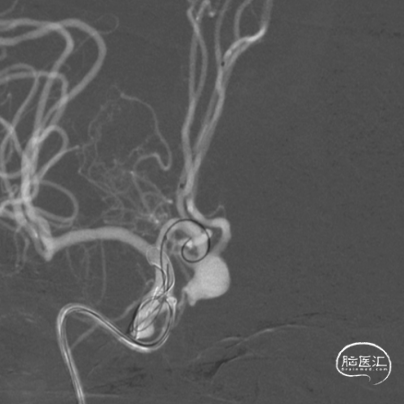

接续填入2枚9mm*30cm弹簧圈,再调整微管位置,送入4mm×12cm、4mm×10cm、3mm×8cm、2mm×6cm弹簧圈。

置入第一枚Atlas支架 3mm×15mm。